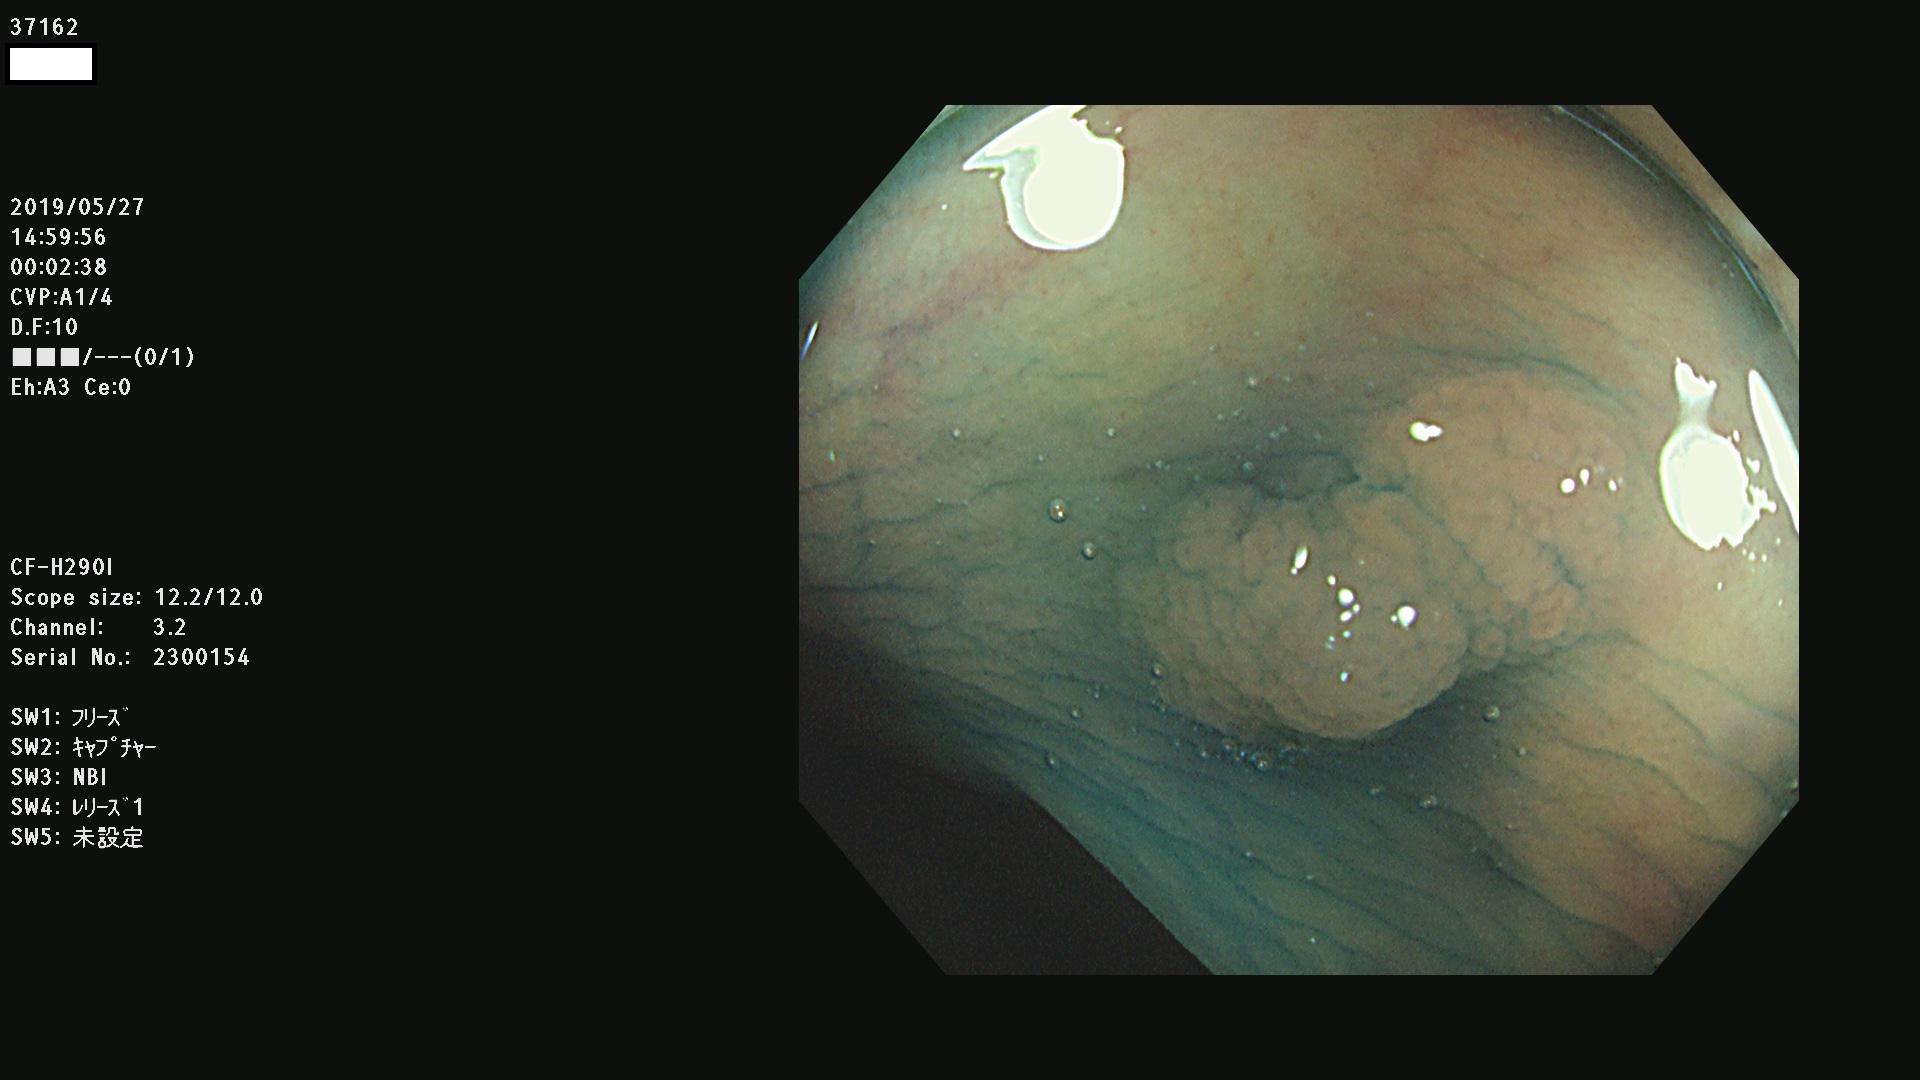

37100 37101 37102 37104 37106 37108 37110 37111 37112 37113 37115 37118(SSAPのみ) 37120 37122 37123 37124 37127(SSAPのみ) 37128(SSAPのみ) 37131 37132 37133 37134 37135 37139 37141 37142 37143 37144(SSAPのみ) 37145 37147(SSAPのみ) 37148 37149 37150 37153 37154 37157 37159 37161 37162 37163 37164 37165 37166 37167 37168 37169 37170 37171 37172 37173 37175(SSAPのみ) 37176 37177 37178 37180(SSAPのみ) 37181 37184 37185 37186 37187 37188 37189 37190 37192 37194 37197 37198

発見困難で危険性の高い平坦型病変(上記100名より抽出)